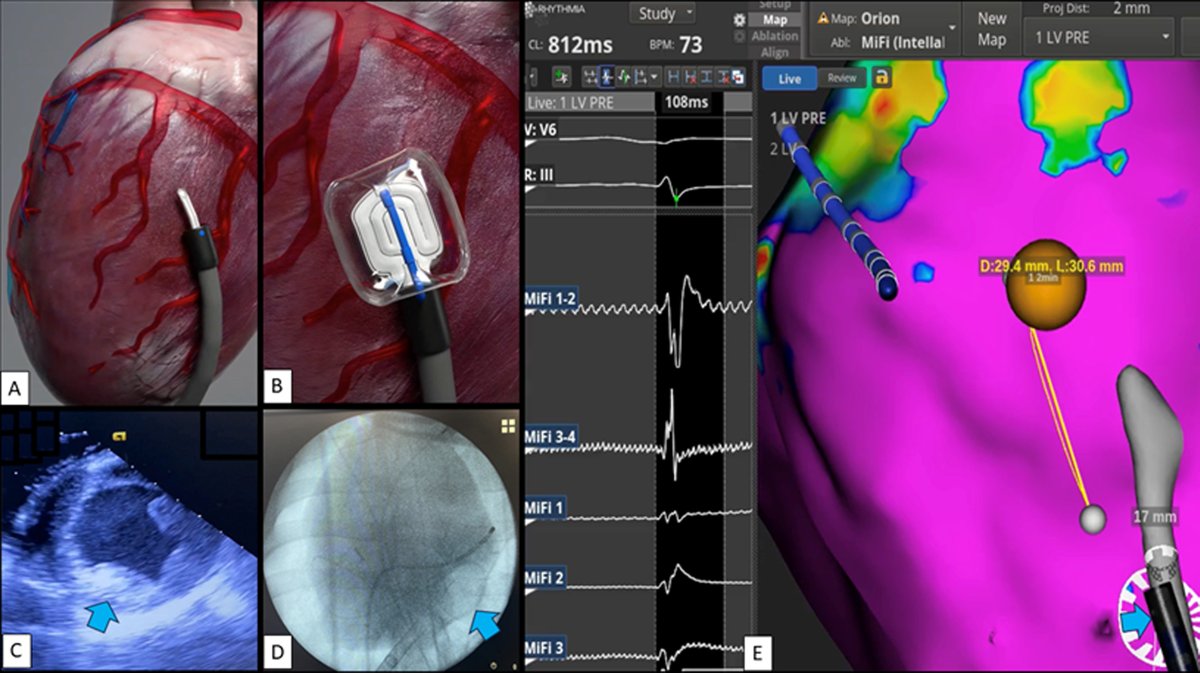

Thank you to Pasquale Santangeli and his team at the Cleveland Clinic AFIC lab for fresh preclinical work with Corfigo's 14Fr percutaneous HeartPad using pericardial wire access. Very promising results!

Epicardial ablation evolution. From Heart Rhythm Society meeting 2023 to recent pre-clinical work at Cleveland Clinic we showed that the HeartPad worked well with percutaneous pericardial access and aggressive device downsizing. Was great to catch up with our team VT Symposium!

Continuing to showcase some aspects of Corfigo, Inc 's recent pre-clinical work with partners at Cleveland Clinic Heart, Vascular & Thoracic , led by Pasquale Santangeli . One of the best things about cryo for percutaneous epicardial ablation is cryoadhesion. Once the tissue-device interface drops below freezing, it